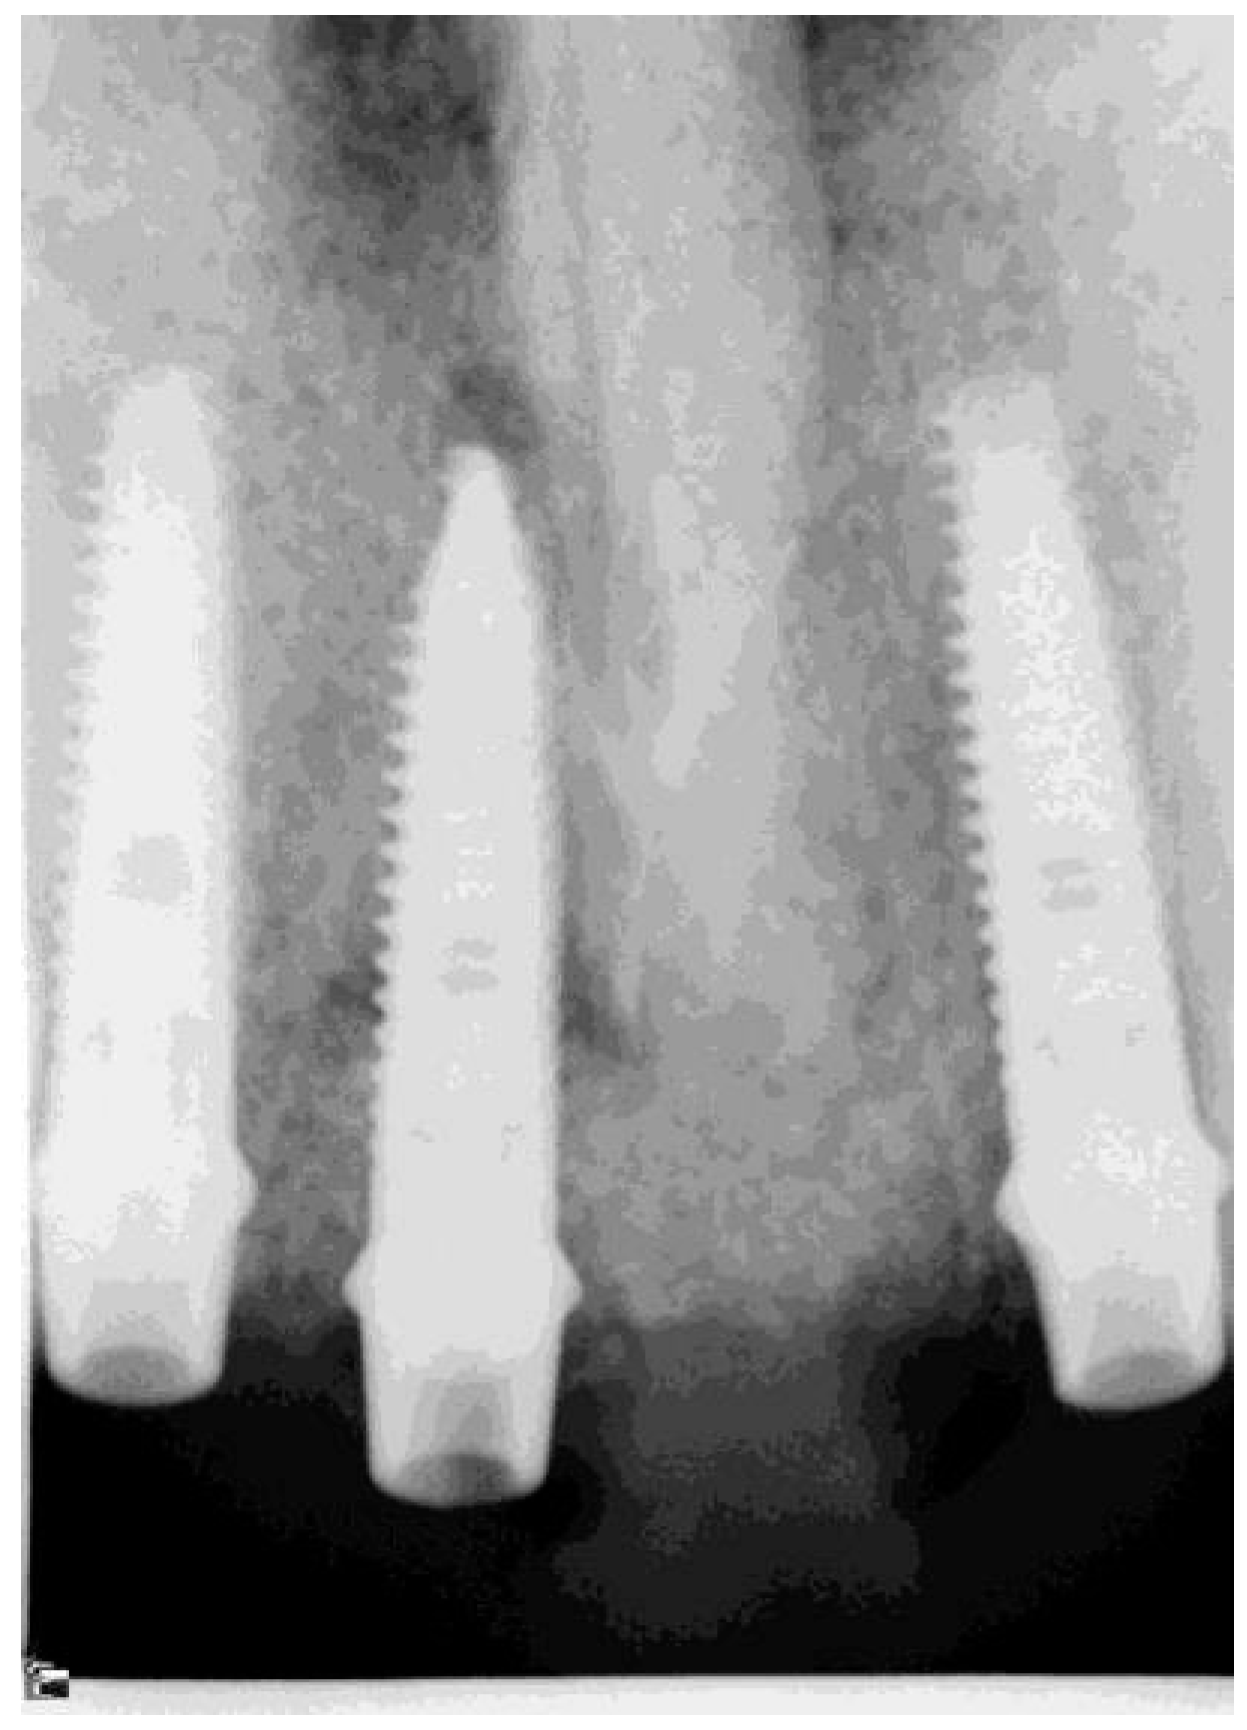

2.6. Follow-Up and Criteria for Success

The patients were seen as part of their routine annual recall program 1–7 years after prosthetic bridge installation. They underwent a clinical examination, and non-standardized radiographs were taken with a paralleling device (Figure 9). The distance between the mesial and distal alveolar bone crest and the implant shoulder (First Bone-to-Implant Contact-DIB) was digitally measured using computerized dental radiography (Schick Technologies, Long Island, NY, USA), based on parallel periapical X-rays. Radiographic distortion was calculated by dividing the radiographic implant length by the actual one. One experienced examiner (AWM) who was not involved in the surgical or prosthetic treatment of the patient performed the radiographic readings.

Figure 9.

Radiographs taken before treatment, at transfer verification, and 40 months after bridge installation. (patient No. 29).